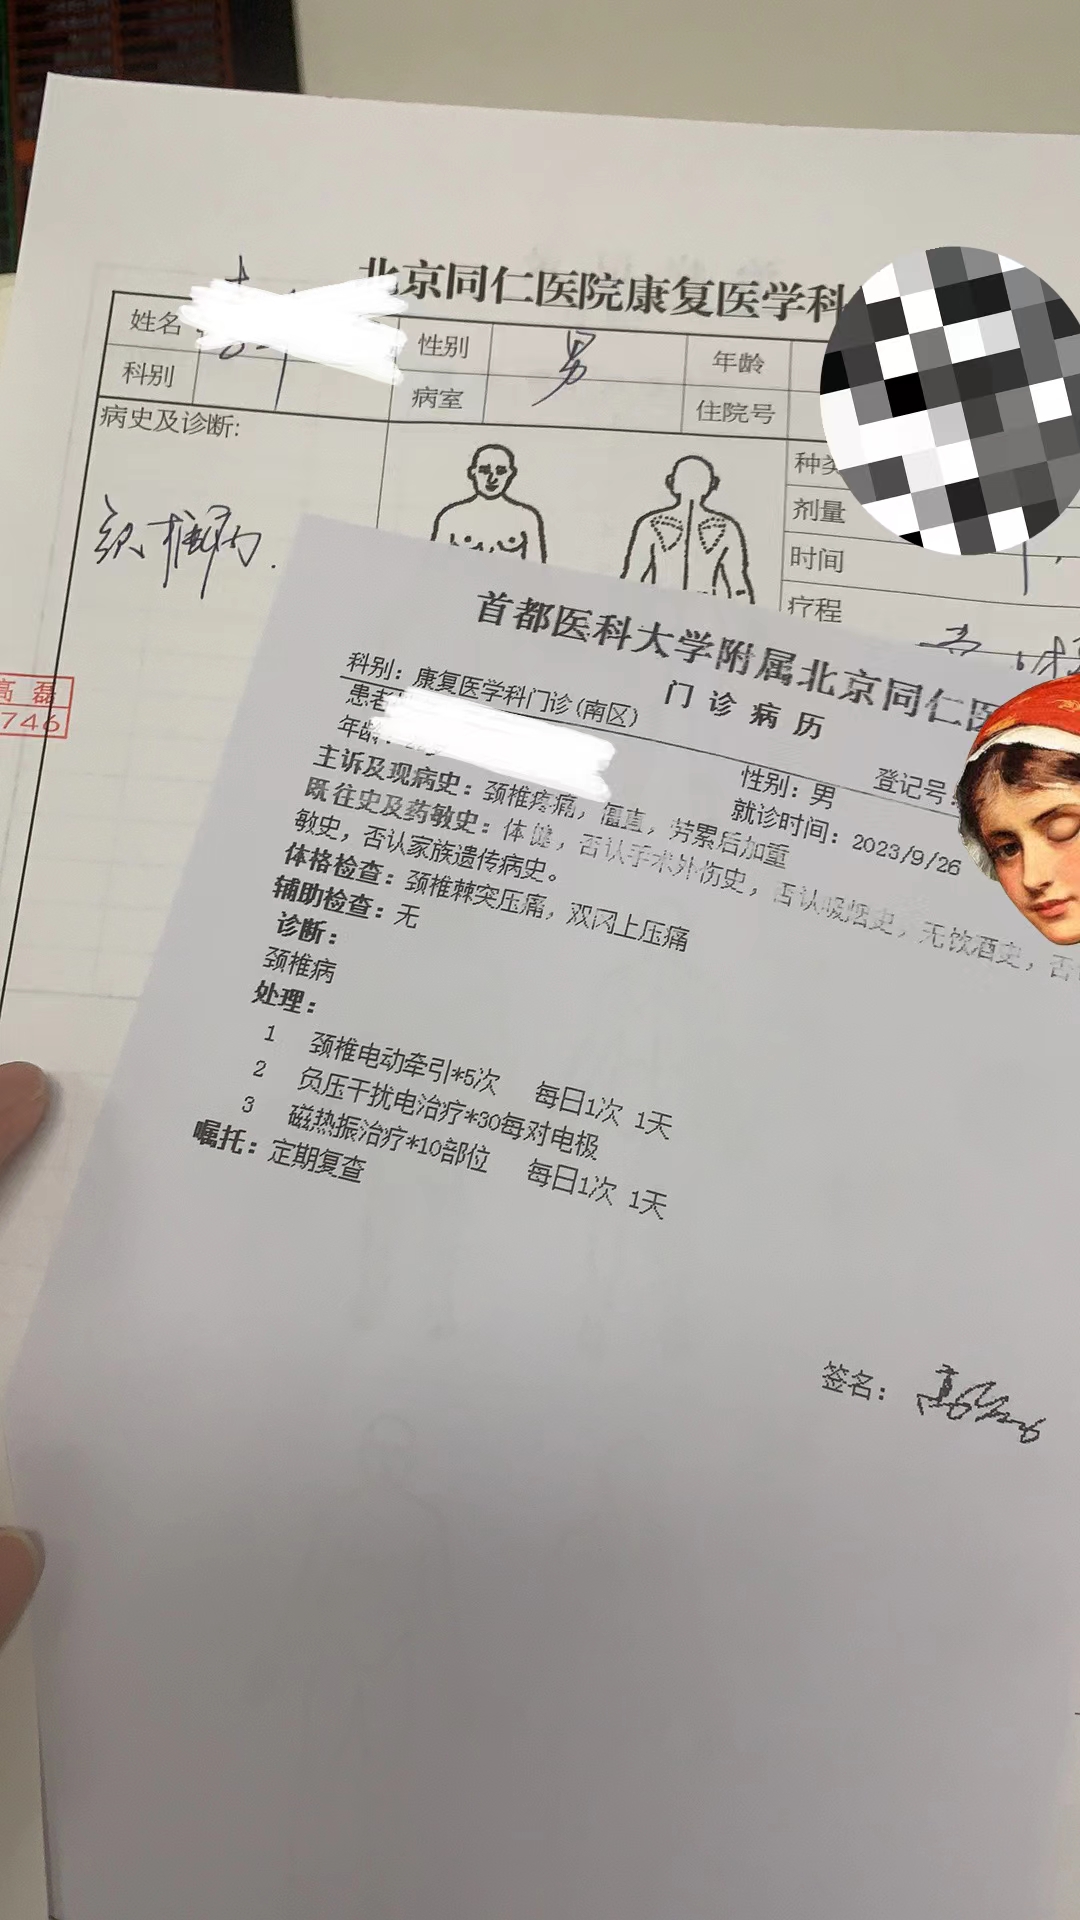

中文:有复杂信息的真实患者诊疗单(幻觉严重)

患者诊疗单(给GPT的是原图,以下图片经过二次处理模糊了患者信息)

有精确性要求的文字工作:如1.1节 患者诊疗单等OCR场景。

1.1 OCR功能(幻觉严重,中文效果差)